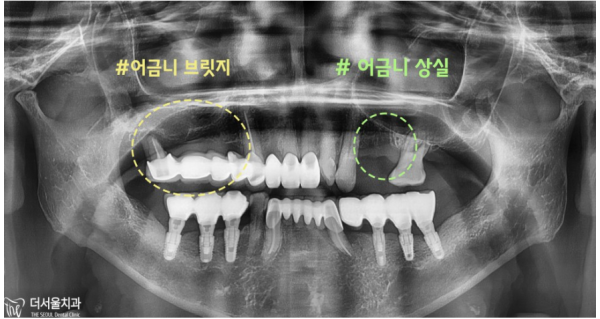

계획대로 임플란트가 잘 마무리되었습니다.

사실 이 환자분은 저희 모란역 더서울치과를 찾아오시기 전에

다른 곳에 가셨는데, 치료가 어렵다는 말씀을 듣고 저희 치과를 찾아오셨습니다.

저희도 실제로 치료를 하면서 많은 걱정을 하고 치료를 하게되었습니다.

치조골이 거의 없는 상태의 환자분들은 뼈이식을 한 후에 픽스쳐를 심게됩니다.

치료에 필요한 시간도 오래 걸리는 고난도의 케이스입니다.